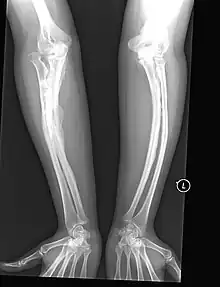

- Encurvamento dos ossos mesmo sem fraturas evidentes;

- Tipo V: Apresentam uma forma moderada da doença com algumas características clínicas e radiológicas distintas, como calcificação da membrana interóssea entre rádio e ulna e/ou tíbia e fíbula, formação de calos hiperplásicos em ossos longos, deslocamento da cabeça do rádio e ausência de dentinogênese imperfeita (DI), mas por mutação do gene IFITM5.

Por ser uma doença que conseguimos ver no fenótipo do portador, há caracteristicas da doença como a esclera azul, dentinogênse imperfeita, déficit auditivo, frouxidão ligamentar, baixa estatura, fragilidade cutânea, cicatrizes hiperplásicas, constipação intestinal, calcificações vasculares e prematuras e doenças na válvula mitral e aórtica, ossos wormianos. No diagnóstico diferencial devem ser consideradas outras doenças como Loyes-Dietz, De Barsy, Marshall-Mitch, e Russel-Silver, em casos clínicos podem ser em casos de alcaptonúria ocronose, síndrome da córnea frágil e malformações múltiplas[4] doença metabólica óssea da prematuridade, osteoporose juvenil idiopática, síndrome de Ehlers‑Danlos, hipofosfatasia, hiperfosfatasia idiopática, síndrome osteoporose pseudoglioma, deficiência de vitamina D e de cálcio[10][11]causas secundárias de osteoporose, incluindo deficiências hormonais, osteoporose induzida por glicocorticoides e leucemia linfoblástica aguda devem ser investigados.[10]Pode também ser confundida com abuso, por conta das fraturas, por isso a importância da avaliação da criança, dos familiares em relação a genética e história clínica para afastar as hipóteses de maus tratos. Fraturas completas ou incompletas da diáfise de ossos longos ou fraturas da coluna vertebral são mais frequentes nos portadores da OI.[4]

Há fontes materiais em arqueologia para fetos intrauterinos com a patologia OI, datando de apenas 38 semanas de gestação. Datado do periodo Bizantino, foi encontrado em Oásis Dakhleh, Egito. Através de uma análise macroscópica e radiológica o esqueleto apresenta uma característica própria de OI com o arqueamento severo dos ossos longos. Este arqueamento é o elemento que resulta na baixa estatura dos indivíduo, é um fator gradual e geralmente apresentado no tipo IV. desta forma, a expectativa de vida de crianças mais gravemente afetadas com OI (tipo II) geralmente não sobrevivem ao período neonatal. Entretando para os tipos I e IV há desenvolvimento pós-nascimento. No tipo III, a expectativa média de vida pode ser encurtada por causa da cifoescoliose grave e formato torácico anormal com doença pulmonar restritiva concomitante e insuficiência cardíaca.[14]